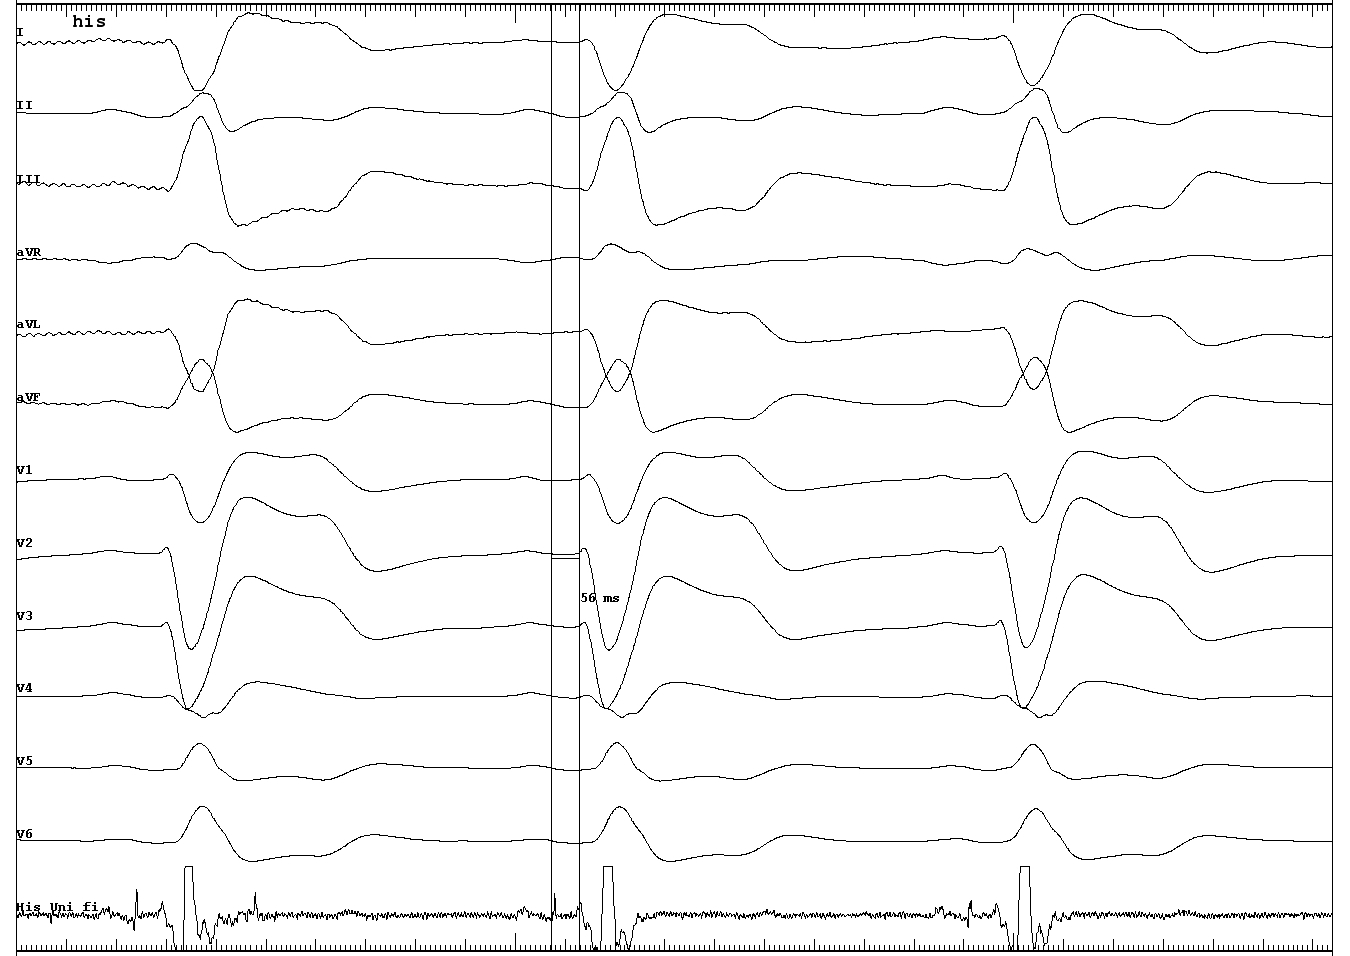

His recording from pacing lead

His.JPG

His capture

His_capture.JPG

LBBB correction at high output

correction_high_output.JPG

Assessing LB capture

• RBBB morphology with unipolar pacing

• LB potential

• LVAT

• V6 to V1 interval